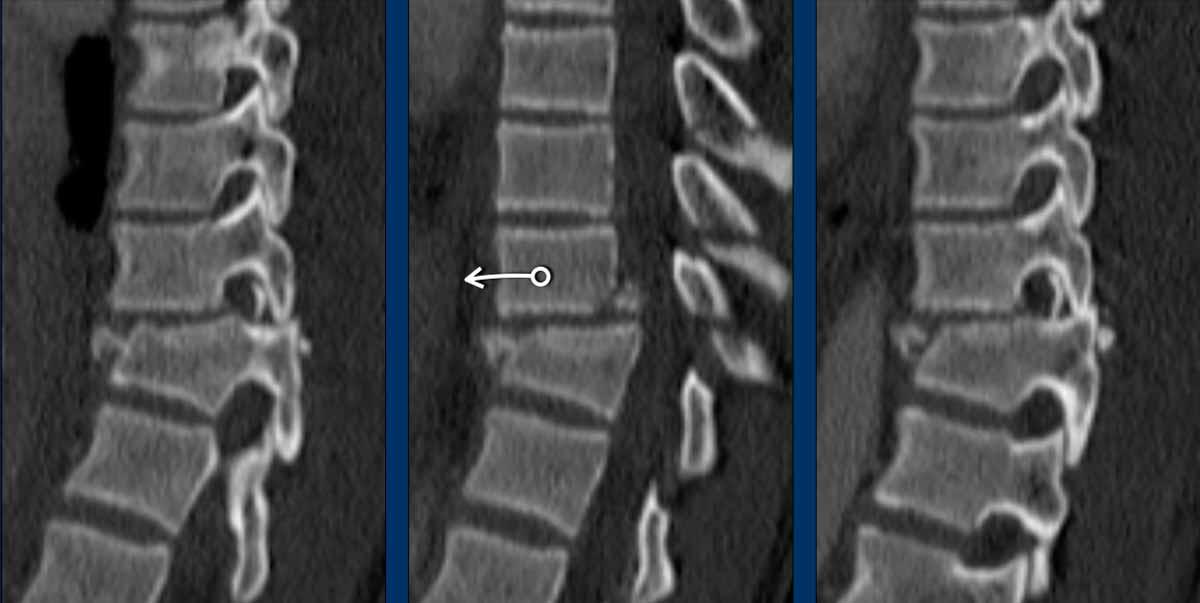

First look at the images.

What are the findings?

What is the highest AO-type of injury?

Findings

- Both facet joints are perched or displaced (black arrows).

The displacement of the vertebrae (white arrow) is not as striking as in previous cases. - There are fractures of the spinous processes on multiple levels.

This is a common feature in C injuries. - Pay attention to the chip fractures on the endplates.

Conclusion

Type C + A1 injury.